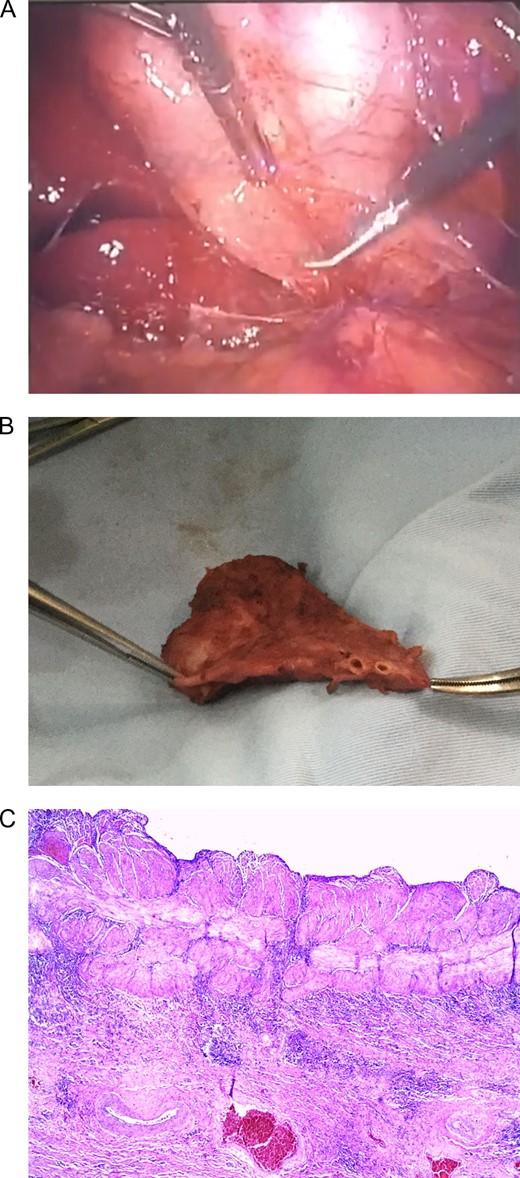

At laparoscopy, multiple adhesions from omentum to the gallbladder fossa were seen and released, revealing the Calot’s triangle structures. After achieving critical view of safety, a gallbladder duplication was identified, the right gallbladder had purulent bile with thickening of its walls, the second gallbladder appeared normal. Both of them had independent cystic ducts, but only one cystic artery was detected (Fig. 2A and Supplementary Video). From there surgery was straightforward, clips were applied to the common cystic duct and cystic artery respectively and they were divided between the clips without any complications. After that, the gallbladders were dissected off the gallbladder fossa using electrocautery and retrieved in a latex bag via the umbilical port.

(A) Laparoscopic view of two gallbladders, each with its’s individual cyst duct and an oedematous wall in one of them. (B) Gallbladder duplication with two independent cystic ducts. (C) Thickened muscular layer and vascular congestion of gallbladder wall.

Pathology reported two permeable cystic ducts, and two separated gallbladders divided by thick inflammatory tissue. Multiple 0.5 cm gallstones were discovered in the left gallbladder and biliary sludge in the right one (Fig. 2B). Microscopically, chronic exacerbated cholecystitis was detected in the right gallbladder (Fig. 2C). A Y-shaped gallbladder duplication with cholecystitis due to cholelithiasis in one of them was the final diagnosis